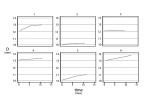

Distances (D) were measured in six different locations at 1 month (baseline-T0), 6 months from baseline (T1), and 12 months from baseline (T2) (Figure 14). All measurements began 5 minutes after removal of the provisional fixed partial denture. Each value was the mean of three measurements for each papilla made by three different blind operators. Mean distances (D) are reported in Table 1.

An estimated panel linear regression model was created with fixed effects, where the mean papilla height (D) was regressed over time to identify the presence of either a decreasing or increasing trend. The model was estimated by grouping the observations into the six different locations (Table 1), disregarding location 3 because it was highly correlated with location 4. Model estimates showed a significant (P value = 0.001) and positive regression coefficient (coefficient = .0497) for the variable time, indicating an increasing trend over a 12-month interval (growth of the papilla). This increasing trend is also evident from the data depicted in Figure 15.

The same model was also estimated by disregarding location 4 instead of 3. The results were similar (P value = 0.004, coefficient = .0453) and reached the same conclusions.

This analysis, being based on a small sample of observations on a single individual, had only a descriptive meaning and the results were encouraging, but no definitive conclusions can be drawn from it.

After the first 12-month data collection, radiographic and clinical follow-up with measurements taken from the fixed reference points were carried out up to 24 months, when the cortical screws were removed. Data recorded at 24 months (distance [D]) were comparable to those recorded at 12 months with no changes in papilla height.